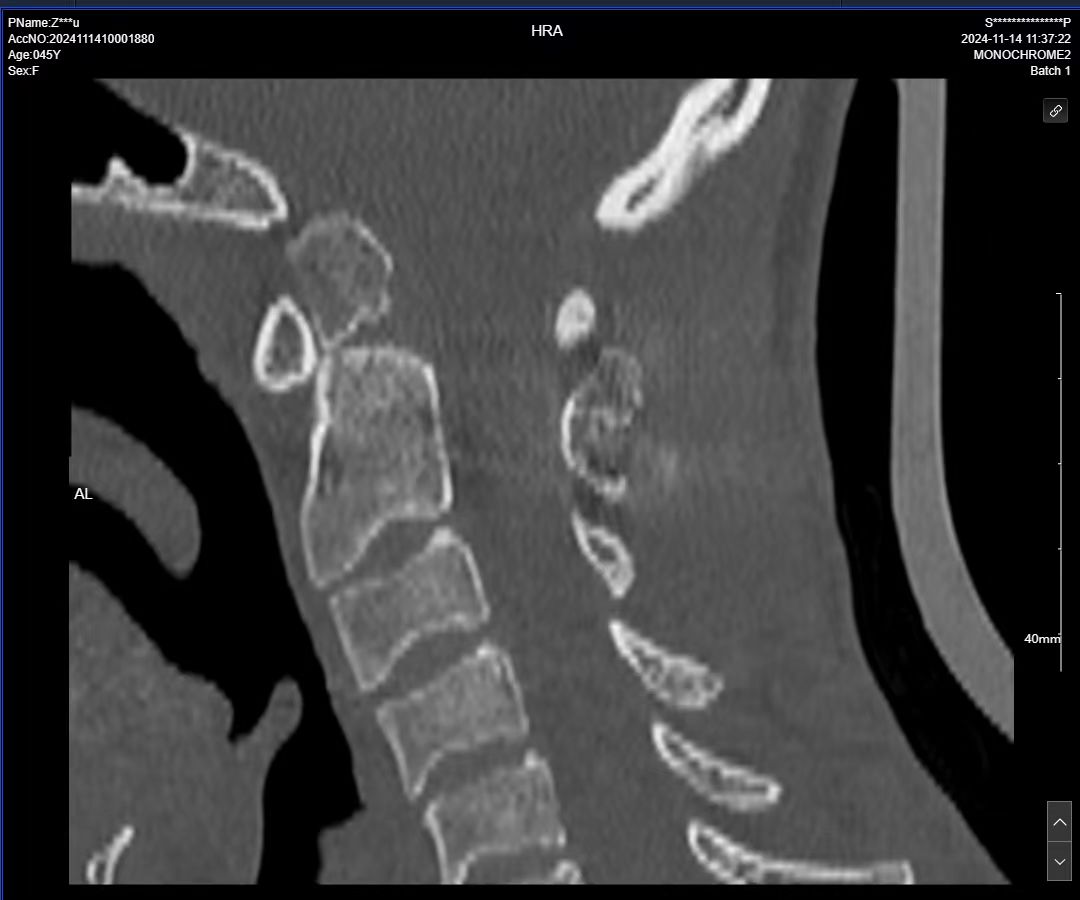

• 术后影像: